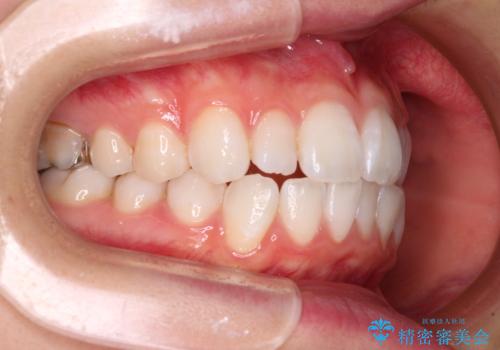

【モニター】口が閉じにくい 膨らんだ口元を抜歯矯正ですっきりと

- 前歯の出っ歯と口元の閉じにくさを気にして来院された患者様です。

口元を積極的に引っ込めるために、上下左右の小臼歯4本を抜歯することとしました。

4本の歯を抜歯したことで、飛び出していた口元が引っ込み、横顔が大きく改善されました。